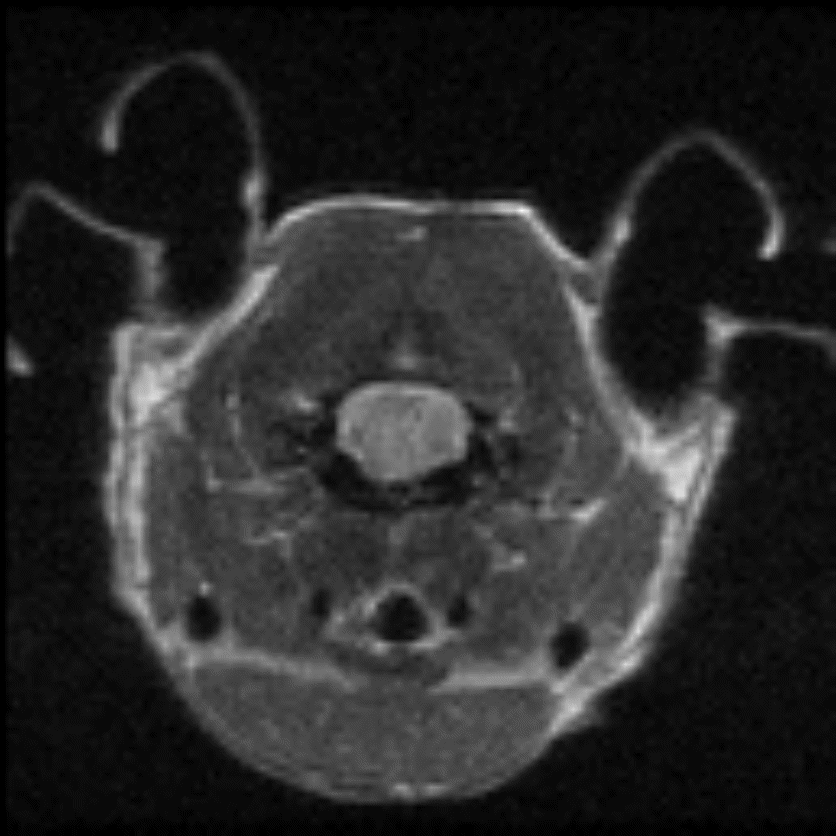

Epilepsy in the rat brain: T2- weighted images of a rat brain 48 hours after induction of epilepsy.

Epilepsy in the rat brain: T2- weighted images of a rat brain 48 hours after induction of epilepsy. Image Credit: Scintica Instrumentation Inc

T2- weighted images of a rat brain 48 hours after induction of epilepsy.

T2- weighted images of a rat brain 48 hours after induction of epilepsy. Image Credit: Scintica Instrumentation Inc